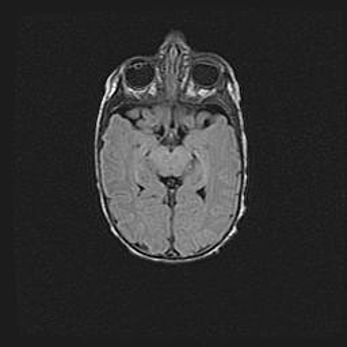

Сообщающаяся гидроцефалия. Кистозная энцефаломаляция головного мозга.

Возраст: 3 месяца 4 дня

Вес: 3100 г

Пол: женский

Окружность головы: 34 см

Срок гестации: 31 неделя

Кистозная энцефаломаляция головного мозга - одна из форм поражения головного мозга в детском возрасте. Характеризуется возникновением множественных и распространённых кист в коре, белом веществе и подкорковых образованиях головного мозга у плодов, новорождённых и детей раннего возраста. Развитие кистозной энцефаломаляции связано с внутриутробной асфиксией и гипотонией, родовой травмой, тромбозом синусов, пороками развития сосудов, инфекциями, сепсисом и другими причинами. Наиболее значимые инфекционные агенты: вирусы простого герпеса, цитомегалии, краснухи, токсоплазмы, энтеробактерии, золотистый стафилококк и другие.